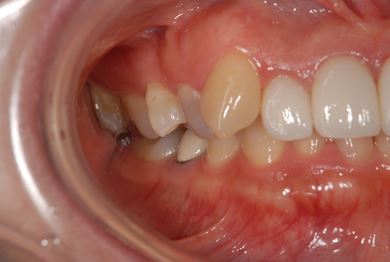

| 性別/年齢 | 女性 / 45歳 | ||||||||||||||||||||||||||||||||

| 主訴 | 右下奥虫歯による冠はずれと、前歯他冠治療済の他の虫歯の有無の確認。 | ||||||||||||||||||||||||||||||||

| 治療方針 | セラミック治療にて、審美的回復を行う。 | ||||||||||||||||||||||||||||||||

| 治療内容 | CAD/CAMオールセラミッククラウン3本(オールセラミック用土台3本)、ハイブリッドセラミックインレー2本 | ||||||||||||||||||||||||||||||||